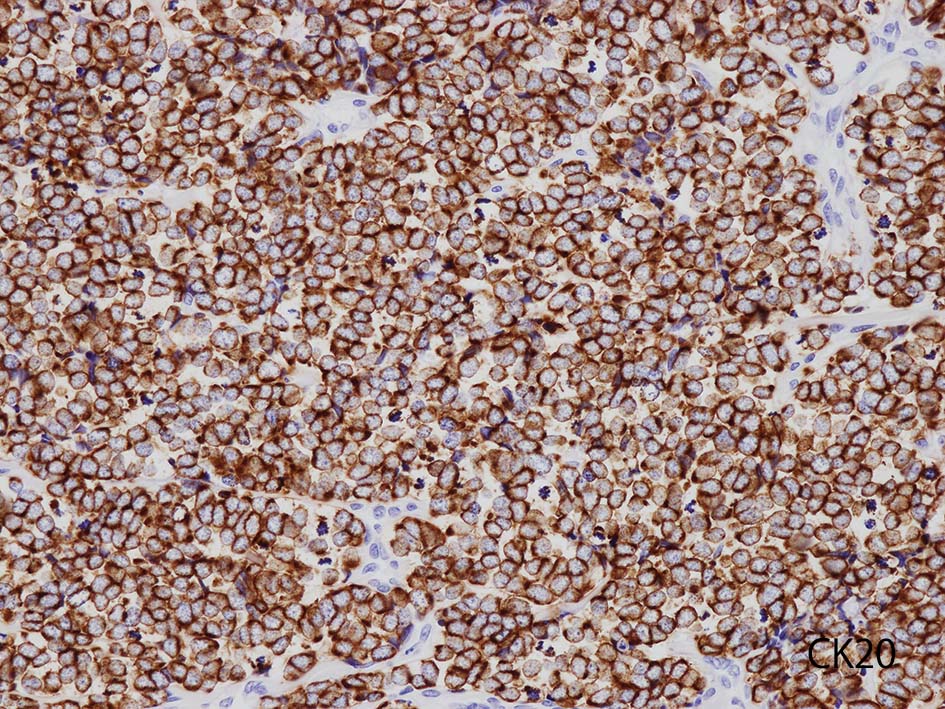

- CK20の染色態度は核周囲にdot状にそまることが特徴的. (MCC[87%]のみではなく肺小細胞癌の4.6%にもこの陽性パターンをみることに注意*2)

CK20

血管を間質にしてround cellsが索状に増殖する所見. rossett様配列がある. CK20は特徴的な dot-like patternを示す. クリックで大きな画像が見られます.

本例では, dot状だけでなく, 細胞周囲にも陽性像が認められる.

CK(AE1/3); CK20は含まない, のほうがdot-likeな染まりをしている. CK20は膜にも陽性になっている. LCAは陰性. 神経内分泌マーカのchromograninA, synaptophysinは陽性.